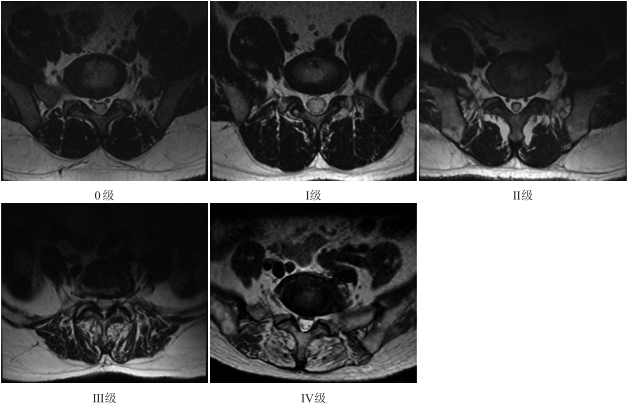

采用腰椎常规T2WI序列横断位,所有的操作均由2名3年肌骨放射诊断工作者协商一致目视评价。腰椎旁肌肉脂肪浸润分级根据Goutallier分级标准[10]:0级为无脂肪浸润,Ⅰ级为少量脂肪浸润,Ⅱ级为肌肉量大于脂肪浸润量,Ⅲ级为肌肉量等于脂肪浸润量,Ⅳ级为脂肪浸润量大于肌肉量(图1)。